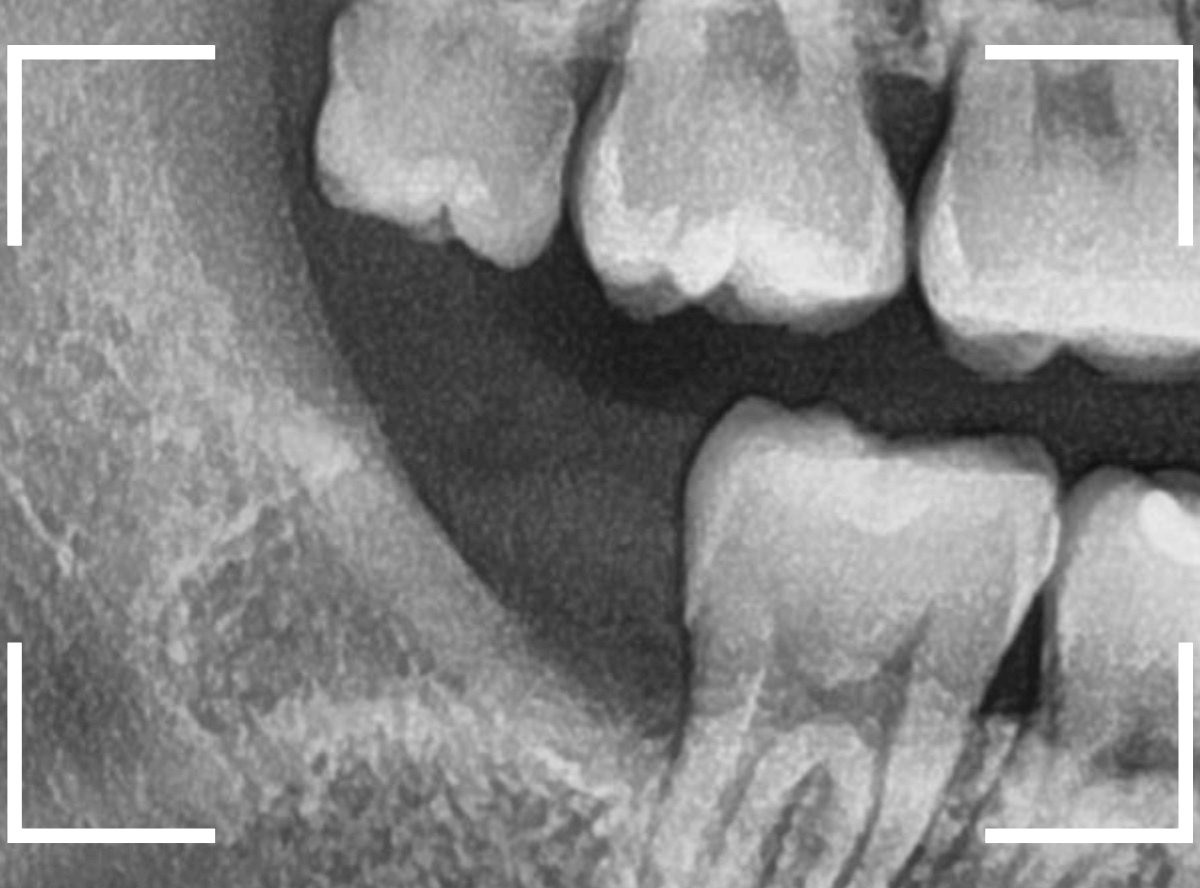

ここでは、比較的簡単なおやしらずの抜歯の例を中心にご紹介します。

このようなおやしらず、あなたはありませんか?